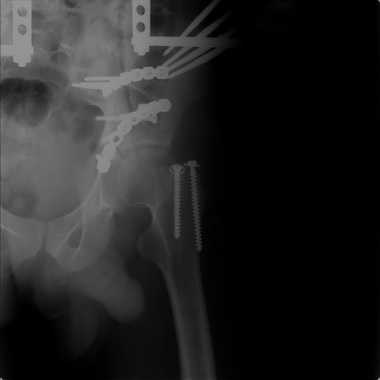

Добрый вечер, уважаемые коллеги. Прошу прощение за долгое молчание( компьютер был в долгосрочном ремонте). Больного с 9-ти месячной травмой таза мы прооперировали. Оценив свои возможности и совместив с вашими рекомендациями и советами (большое спасибо Рункову!), пошли задне-наружным доступом, с отсечением большого вертела. Закрепились 2-мя пластинками. Сверху закрепили аппаратом( передней рамой). На область перелома самого гребня повздошной кости не вмешивались. Снимки высылаю. Жду ваших отзывов и комментариев. Всем большое спасибо за активное участие в лечении больного. С ув.Андрей

Для чего аппарат? Или вы не уверены в стабильности вашей внутренней фиксации? Выглядит достаточно стабильно, аппарат позволит всего лишь чуть ранше дать нагрузку, и всё?

Внутренняя фиксация получилась достаточно стабильная.А передняя рама наложена с целью дополнительной фиксации для нейтрализации мышц прикрепляющихся к крылу подвздошной кости, и исключить возможное расшатывание и возникнование нестабильности внутрених фиксаторов( уж очень большая нагрузка на эти 2 пластины).На открытом этапе операции мобилизовали только часть линии всего перелома( около 1/4 части начиная от свода и проксимально), а остальная часть находится в рубце и патологическая подвижность в ней есть хоть и не выражена) А о ранней нагрузке никто и не думал. А как на ваш взгляд, в какие сроки в такой ситуации разрешить полную нагрузку? Я считаю, что только при сращении перелома, подвержденные лучше бы КТ